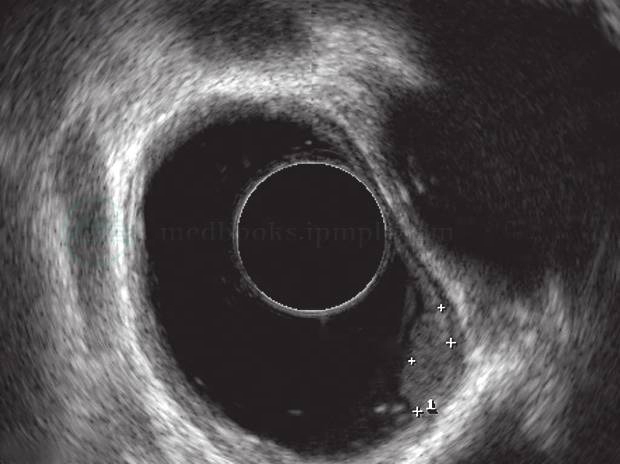

4. 内镜下脂肪瘤常为局部息肉状隆起,表面黏膜往往形态如常,色泽苍白或偏黄。超声内镜下可见边界清晰、起源于黏膜下层的均匀高回声团块(图3-11)。

图3-11 食管脂肪瘤